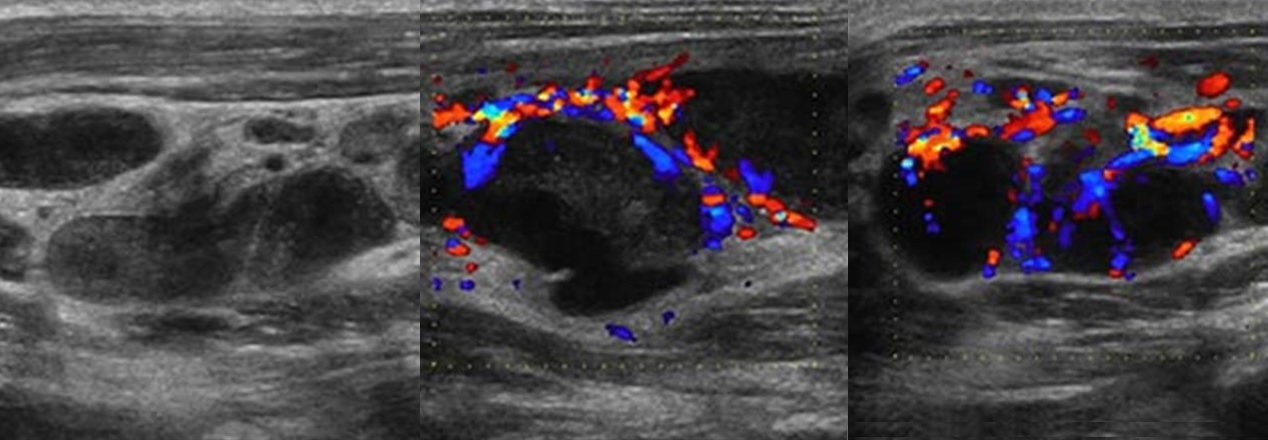

Мезентериальные лимфатические узлы: УЗИ и диагностика